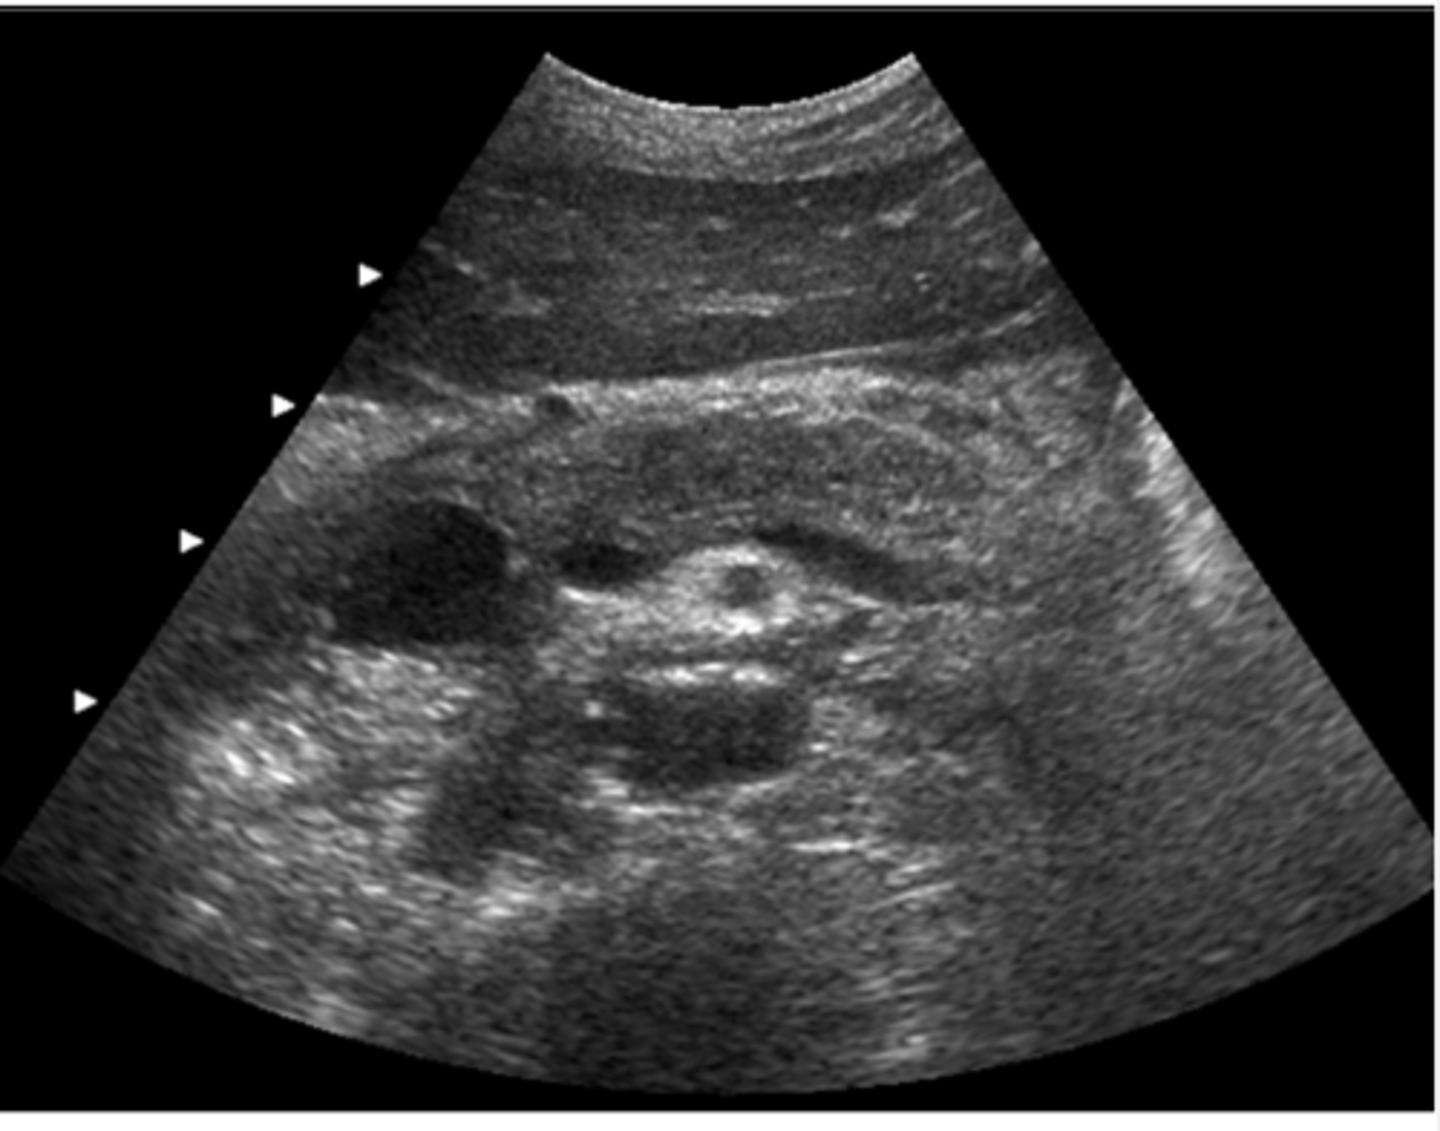

This transverse image was obtained in the mid abdomen of a 57- year-old male with lower back pain. Which of the following correctly describes the sonographic findings?

a. leaking abdominal aortic aneurysm with hematoma

b. abdominal aortic aneurysm and para-aortic lymphadenopathy

c. inflammatory abdominal aortic aneurysm

d. abdominal aortic aneurysm and horseshoe kidneys

e. abdominal aortic aneurysm with retroperitoneal fibrosis